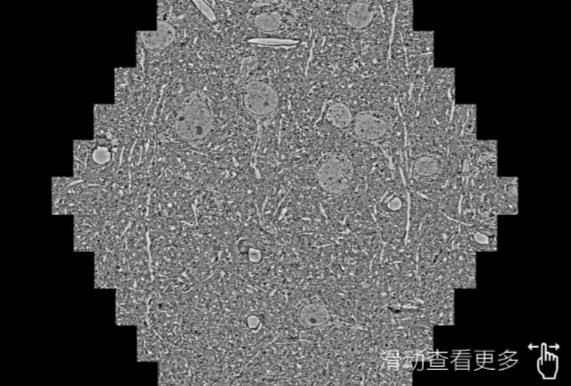

鼠脑切片。左图使用长寿蔡司长寿扫描电镜MultiSEM706对165μmx143pm面积区域成像,耗时仅需1.5秒。右图为鼠脑切片中30μm区域放大效果。样品由芝加哥大学B.Kasthuri提供。